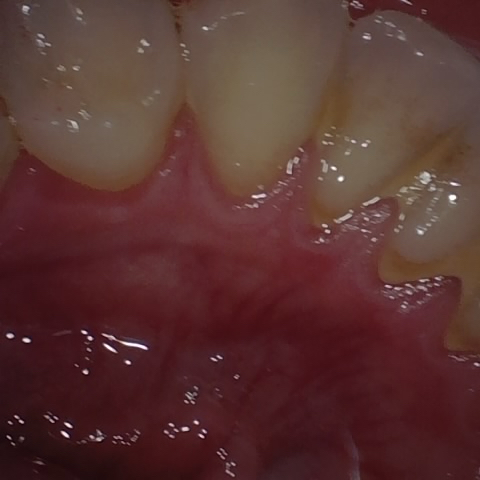

Annotated as "Good"